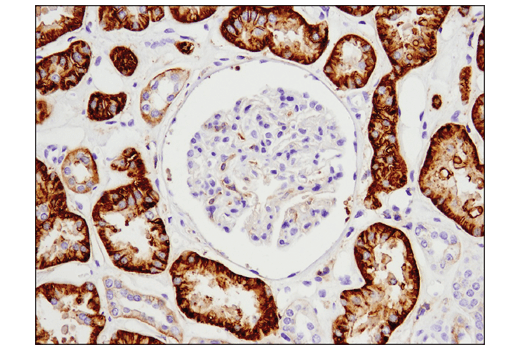

Immunohistochemical analysis of paraffin-embedded normal human kidney using 4F2hc/SLC3A2 (D5U4G) XP® Rabbit mAb.

Immunohistochemistry Image 2: 4F2hc/SLC3A2 (D5U4G) Rabbit Monoclonal Antibody